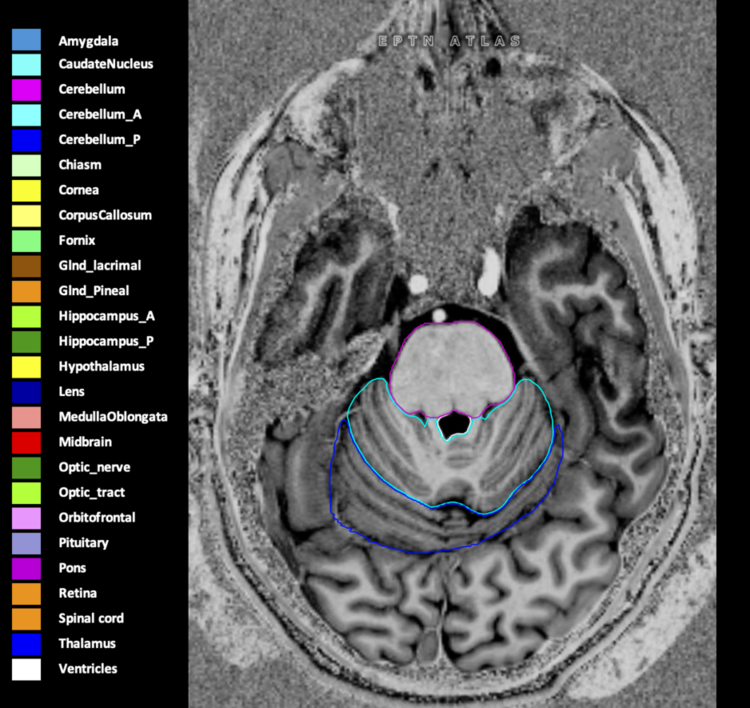

Eekers et al. have published an international neurological atlas for contouring of organs at risk in consensus with the European Particle Therapy Network (EPTN) in 2018 and an update in 2021. The purpose of this consensus atlas is to decrease inter- and intra-observer variability in delineating OARs relevant for neuro-oncology.

Included are all OARs known to be relevant for radiation-induced toxicity in neuro-oncology: brain, brainstem (midbrain, pons, medulla oblongata), chiasm, cerebellum (anterior & posterior), cochlea, cornea, hippocampus (anterior & posterior), hypothalamus, lens, lacrimal gland, optic nerve, pituitary, skin, and vestibular & semicircular canals. To further facilitate research on cognition, vision and radiological changes after irradiation of the brain, potential clinically-relevant OARs are included: amygdala, caudate nucleus, cerebellum (anterior & posterior), corpus callosum, fornix, macula, optic tract, orbitofrontal cortex, periventricular space (PVS), pineal gland, and thalamus.

Three-dimensional delineation of the 25 consensus OARs for neuro-oncology are shown on CT (WW/WL 120/40, 3000/600), 3T MR images, (T1Gd, T2FLAIR 1mm) and 7T MR (MP2RAGE 0.7 mm). All are presented in transversal, sagittal and coronal view.